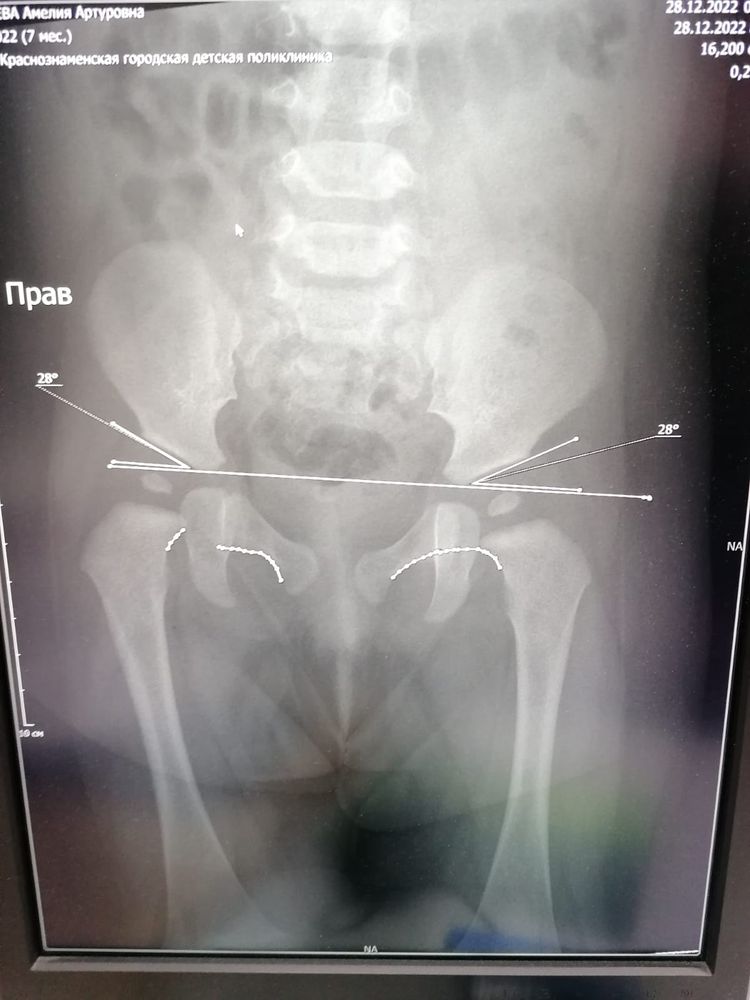

Малышке 7,5 месяцев, прошли второй курс массажа и на массаже мне сказали,что надо сходить к ортопеду,массажистке не понравилась правая ножка у малышки. Мы пошли к ортопеду,он осмотрел визуально нас,сказал,я ничего не вижу,но сходите на рентген. Пошли га рентген и там описали снимок,дали заключение вывих правого тазобедренного сустава ножки под вопросом. Дали нам направление на осмотр в клинике ортопедии и травматологии в Москве. Сегодня поехали туда,там нас осмотрел ортопед и невролог. Ортопед сказал,что визуально складочки на ножках не равномерно и правая ножка короче левой на 0,5 см, посмотрела наш снимок рентгена и сказала,что по снимку нет дисплазии. Сказала,что это тонус такой,мышечная недостаточность так сказать,ничего страдного,сказала делать массажи,плаванье,парафин и электрофорез.

Вот прикрепиляю снимет рентгена и заключение ортопеда и невролога из Москвы на сегодняшнем осмотре. Я вот вроде немного успокоилась,врач сказал никаких шин и распорок в нашем случае не нужно. Разве из-за тонусу может быть ножка чуть короче другой и неравномерные складочки. Думаю что делать дальше,можно успокоится или еще раз сделать снимок. Может у кого-то была похожая ситуация